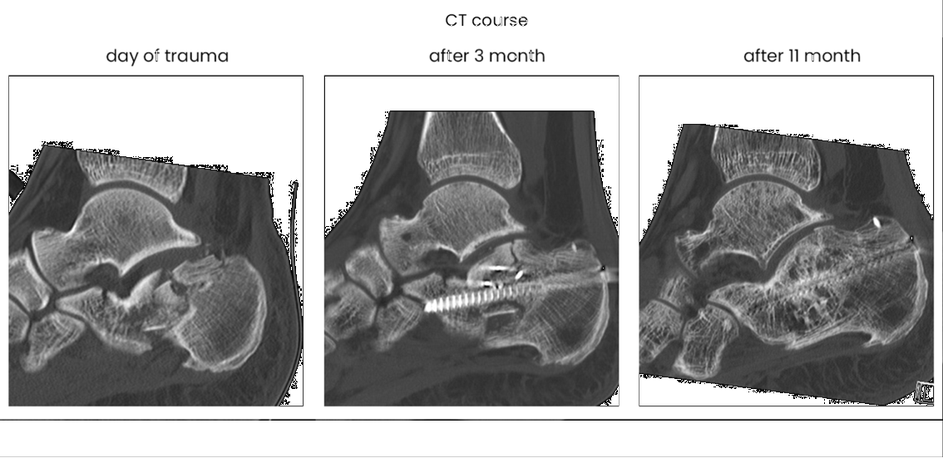

case 17BD, 47 years old, male, fall during work, 2 meters, "comminuted fracture", surgery after 2 days